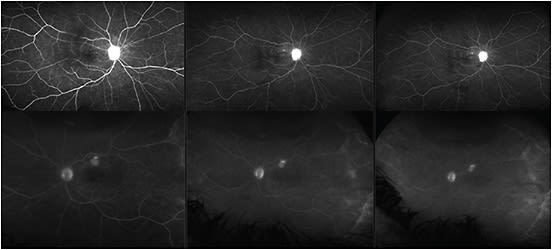

The retinal detachment was repaired with scleral buckle placement and pars plana vitrectomy using perfluoro octane gas (PFO), air fluid exchange, 360-degree endolaser, and placement of 14% C3F8 gas. The patient had a normal postoperative presentation until 8 weeks post-op, when she started to complain of severe headaches that progressed to vision loss in the fellow (right) eye. At this point, anterior chamber inflammation and vitritis became visible in both eyes, with small pockets of submacular fluid collections and choroidal lesions seen on fluorescein angiography (Figure 1). Her vision had dropped to 20/100 in the right eye and 20/200 left eye.

The severity of inflammation can vary. Anterior segment findings include mutton-fat keratic precipitates, thickening of the iris, and posterior synechiae. Posterior segment findings consist of vitritis, Dalen Fuchs nodules, peripapillary choroidal lesions, and exudative retinal detachment. Early in the disease, a fluorescein angiogram will typically show multiple areas of punctate hyperfluorescence (starry sky) with leakage and pooling at areas of neurosensory detachment of the retina. ICG will demonstrate multiple areas of hypofluorescent foci; and on OCT, serous retinal detachments with intraretinal edema will be evident. Choroidal thickening can also be detected on B-scan.